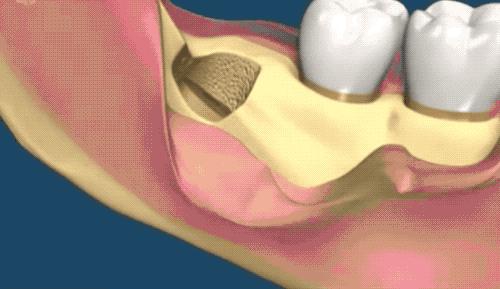

露出牙槽骨后,先削除一部分骨头,露出躺卧如睡美人的横阻生智齿...如果是已经出肉的智齿,就没这一步了。

请出那令人闻声丧胆的牙科涡轮机,先分割智齿,撬出块头过大的牙冠来...再把牙根磨切两半,依次撬出来。当然这样的操作并不都是必须的,牙医会依据当时的可操作性去处理,毕竟每个哈姆雷特的横阻生智齿也都可能长得不一样。

小编的智齿是还粘连了一部分肉,拔出来一些后,医生又换手术刀把粘连的肉从智齿上切断...牙医操作的时候,总跟动画片主角放大招一样,每次都要跟护士报工具名,刺激的小编真想要捂住嘴巴。